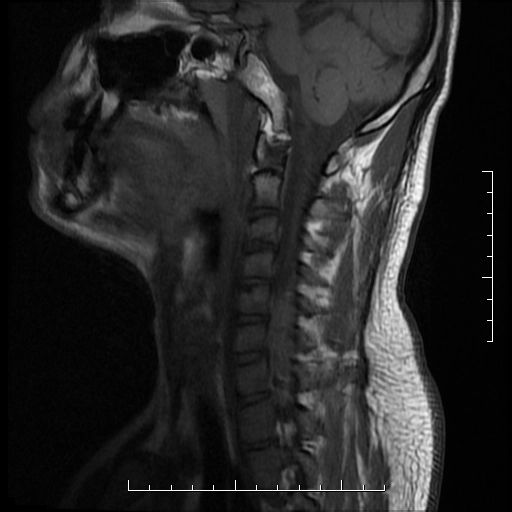

Tổn thương tủy sống do chấn thương (Traumatic spinal cord injury)